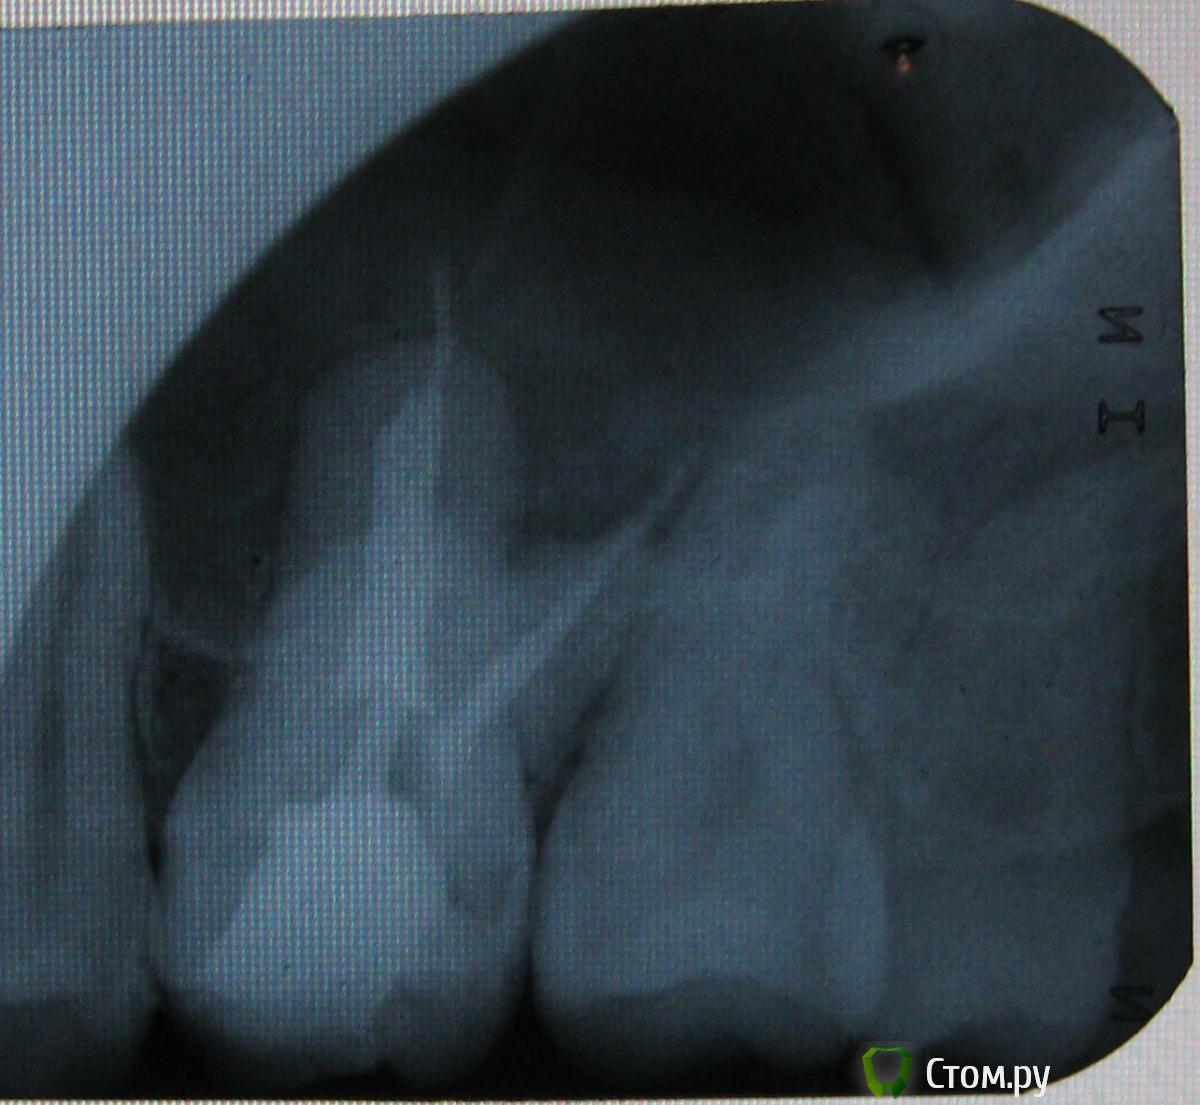

b69 Опубликовано 11 ноября, 2011 Автор Поделиться Опубликовано 11 ноября, 2011 (изменено) Вот запломбировали каналы, врач сказал что они "не очень". Что вы можете сказать про них по снимку?И ещё вопрос, почему даже если уже начался пульпит зуб может не болеть? Изменено 11 ноября, 2011 пользователем b69 Ссылка на комментарий